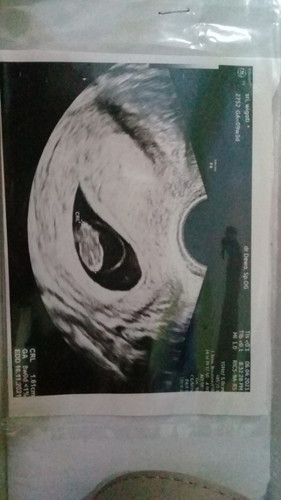

Hamil lagi pasca BO

Bun mau tanya nih barangkali ada yg kasusnya sama..kehamilan pertamaku dinyatakan BO padahal ada bakal janin didalam kantung kehamilan tapi dokter menyatakan BO karena tidak ditemukan detak jantung saat itu uk. 9 minggu...sekarang saya sedang hamil yg kedua semoga sehat selalu..barangkali ada yg sama gimana nih kehamilan kedua ibu2 pasca BO?